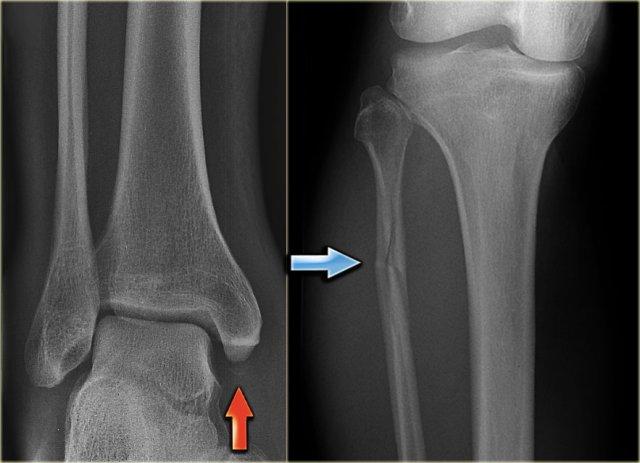

Thoạt nhìn, hình ảnh này có vẻ giống gãy xương Weber B với đường gãy chéo ở xương mác quan sát thấy trên tư thế chụp nghiêng (mũi tên đen).

Tuy nhiên, cần lưu ý rằng đường gãy này dừng lại ở mức sụn tiếp hợp.

Đây chính là đường gãy hành xương trên mặt phẳng trán.

Trên tư thế chụp thẳng (AP), có thể thấy một vùng thấu quang trong lòng đầu xương, tương ứng với đường gãy đầu xương trên mặt phẳng đứng dọc.

Cũng cần chú ý rằng sụn tiếp hợp phía trong đã đóng, trong khi phần ngoài vẫn còn mở (mũi tên xanh).

Chúng ta cần giả định rằng có hiện tượng tách sụn tiếp hợp (epiphysiolysis) ở phần ngoài này.

Đây là một ví dụ khác.

Mảnh gãy hành xương rất nhỏ, đây thường là trường hợp hay gặp (mũi tên đỏ).

Đường gãy qua đầu xương được chỉ thị bằng mũi tên xanh.